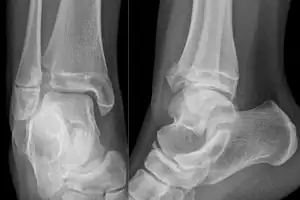

X-ray of a Tillaux fracture in an 11 year old female

A Tillaux fracture is a Salter–Harris type III fracture through the anterolateral aspect of the distal tibial epiphysis.[1] It occurs in older adolescents between the ages of 12 and 15 when the medial epiphysis had closed but before the lateral side has done so,[2] due to an avulsion of the anterior inferior tibiofibular ligament, at the opposite end to a Wagstaffe-Le Fort avulsion fracture

• X-ray ( Anteroposterior, lateral, and Mortise views)